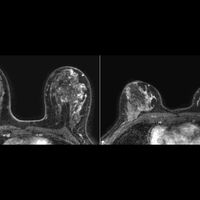

Система искусственного интеллекта (ИИ) обнаружила почти треть агрессивных опухолей, которые остались незамеченными при ручной диагностике. К такому выводу пришли ученые Гарвардского университета. Результаты исследования представлены Радиологическим обществом Северной Америки (RSNA).

Чтобы проверить эффективность ИИ, исследователи проанализировали около 1,4 тысячи томографических изображений, включая 224 случая опухолей, не замеченных врачами. ИИ корректно идентифицировал 73 из них — это 32% от всех пропущенных диагнозов.

Как рассказала доцент Гарвардского университета Маниша Баль, ИИ не только выявил скрытые опухоли, но и точно определил их границы.